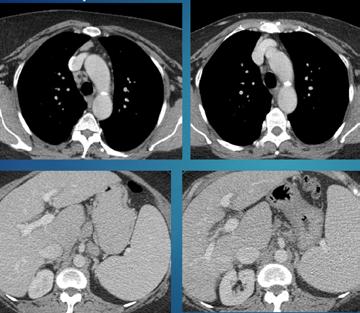

• Studiul opacifierii ramurilor corticale ale arterelor cerebrale medii (M4) drepte și stângi și a venelor cerebrale interne drepte și stângi (Fig.1).

Fig.1 ACTMS cranio-cerebrală, recon MIP în plan axial (a,b) și sagital (c): aspect normal; (a) opacifierea arterelor temporale dreaptă și stângă (săgeţi); (b) opaciferea ramurilor corticale ale arterelor cerebrale medii (M4)-săgeţi albe; opaciferea venelor cerebrale interne dreaptă și stângă (săgeţi negre-b și c).

Semiologie:

▶ Absența opacifierii M4 = 1 punct

▶ Opacifierea M4 = 0 punct

▶ Absența opacifierii venei cerebrale interne = 1 punct

▶ Opacifierea venei cerebrale interne = 0 puncte

• Un scor egal sau mai mare de 3 confirmă stopul circulator intracerebral. In acest caz, concluzia examinării este: „stop circulator intracerebral” care vine în sprijinul diagnosticului clinic de moarte cerebrală sau aspect ACT compatibil cu moartea cerebrală

• În caz contrar, concluzia examinării este „absența opririi circulatiei intracerebrale”, situaţie în care diagnosticul clinic de MC nu este confirmat.

În cazul opacifierii unilaterale a uneia dintre cele două artere cerebrale medii, diagnosticul de MC poate fi afirmată dacă este absentă opacifierea venelor cerebrale interne (Fig,2).